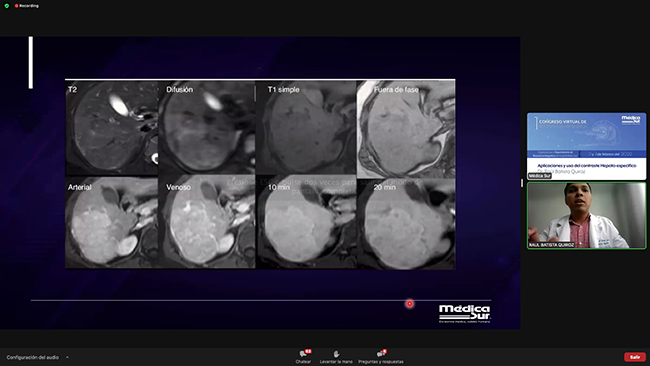

13:30 - 14:00 · Aplicaciones y uso del contraste hepato-específico

Dr. Raúl Batista Quiroz